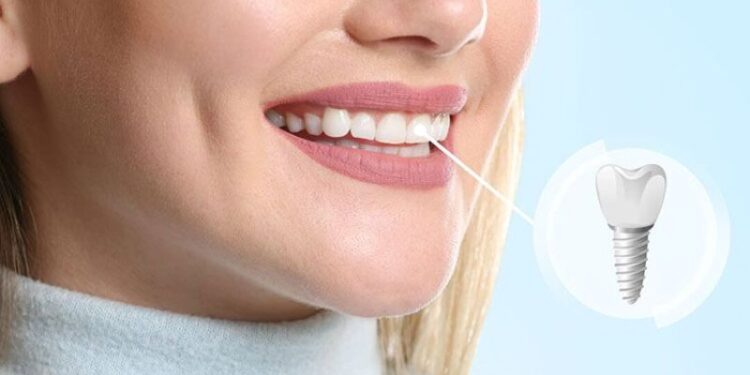

ایمپلنت دندان چیست؟ لبخند زیبا و طبیعی

ایمپلنت دندان در واقع نوعی پروتز کاشتنی است که دندانپزشکها از آن برای جایگزین کردن دندانهای مصنوعی استفاده میکنند. معمولا زمانی که فرد به پزشک مراجعه میکند و دندانهایی دارد که بر اثر آسیبدیدگی از بین رفتهاند، پزشک این روش را پیشنهاد میدهد. ایمپلنتها با قرار گرفتن در بافت زیر لثه و استخوان فک مانند یک دندان طبیعی بهنظر میرسند. در واقع، ایمپلنت همان پیچ فلزی است که درون استخوان لثه قرار میگیرد و پس از گذشت چند ماه با بافت لثه پیوند میخورد. این پیچ بهگونهای طراحی شده که بیشترین سازگاری را با فک شما داشته باشد و هنگام غذا خوردن احساس راحتی خواهید داشت. بهتر است برای ایمپلنت، پزشکی را انتخاب کنید که مهارت کافی درزمینه کاشت فوری ایمپلنت در تهران را داشته باشد. چراکه با انتخاب ایمپلنت مناسب لبخند زیباتری خواهید داشت.

در یک جمله، ایمپلنتها ساختاری دارند که جایگزین دندانهای آسیبدیده میشوند. دندانپزشک در یک جراحی ۲۰ تا ۴۰ دقیقهای با استفاده از دستگاههای پیچی، ایمپلنت را داخل فک قرار میدهد. در ادامه جراحی، با استفاده از دستگاهی به نام اباتمنت، دندانمصنوعی را به ایمپلنت در فک متصل میکند. پزشک این دندانمصنوعی را سفارشی و متناسب با اندازه فک هر فرد طراحی میکند تا با رنگ و سایز سایر دندانها هماهنگ باشد. همچنین جنس پایه ایمپلنت که در فک قرار میگیرد از تیتانیوم است که کاملا با جنس دهان و فک سازگاری دارد و آسیبی به دندانها وارد نمیکند.